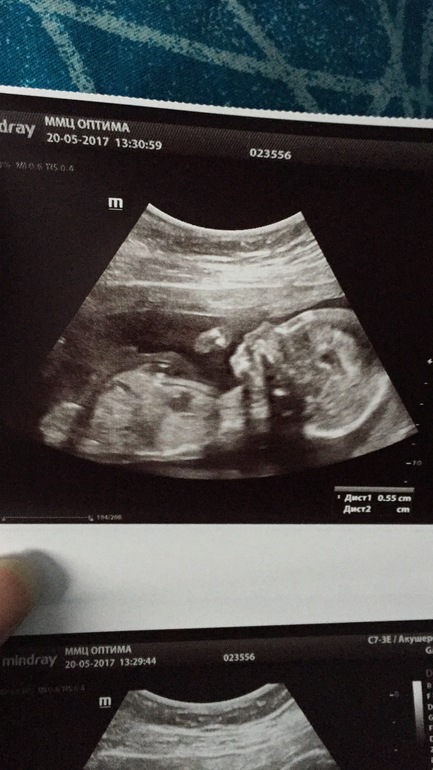

Вот я и дождалась 2 скриннинга. Так быстро летит время. Пошла рано в платную клинику. Стоимость 1300. Все показали и рассказали моего сыночка. Мой сладенький мальчик. Кувыркался в итоге , что бы посмотреть и намерить заняло час, час 20. Была с мужем. Счастлив как слон. Патологий не выявили. Тьфу тьфу тьфу. Кто ещё мне будет говорит что после зб нельзя сразу беременеть, посмотрите на это чудо. Целый день маму пинает и мстит за то что потревожили. Фото УЗИ подкат.

О, поздравляю! На первом фото ручку у ротика держит))) Тоже жду свой скрининг на днях.